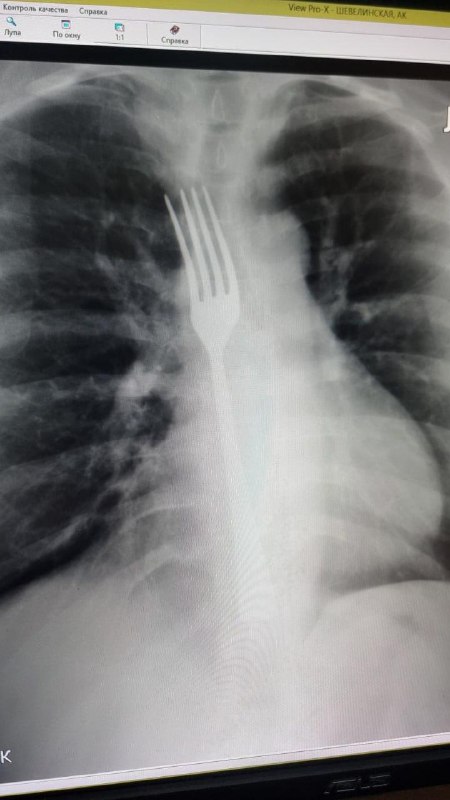

В Витебске женщина проглотила вилку, пытаясь «полечиться» дома